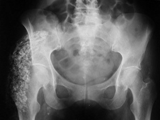

AVN-hips

AVN-hips